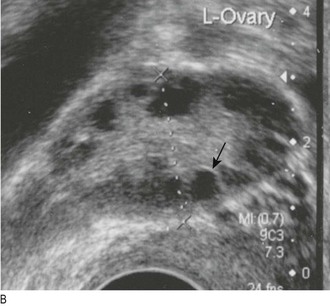

Hirsutism is common in women with polycystic ovary syndrome (Fig. 5.19). Virilisation is temporal recession of the scalp hair, deepening of the voice, breast atrophy, increased muscle bulk and clitoromegaly (Fig. 5.20). If present in women with a short history of severe hirsutism, it suggests a possible testosterone-secreting tumour.